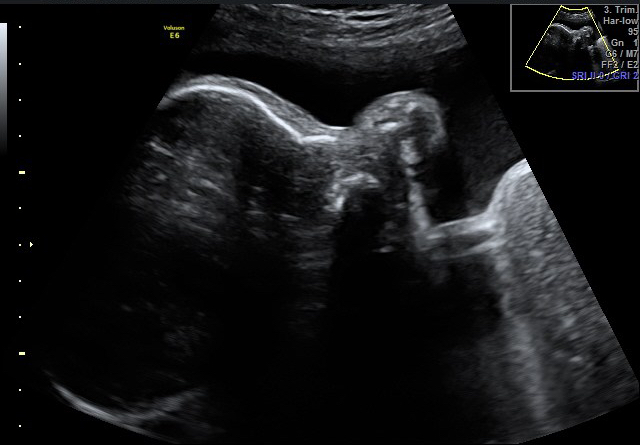

come una mamma aspetta quell’ecografia

Click dentro al pancione